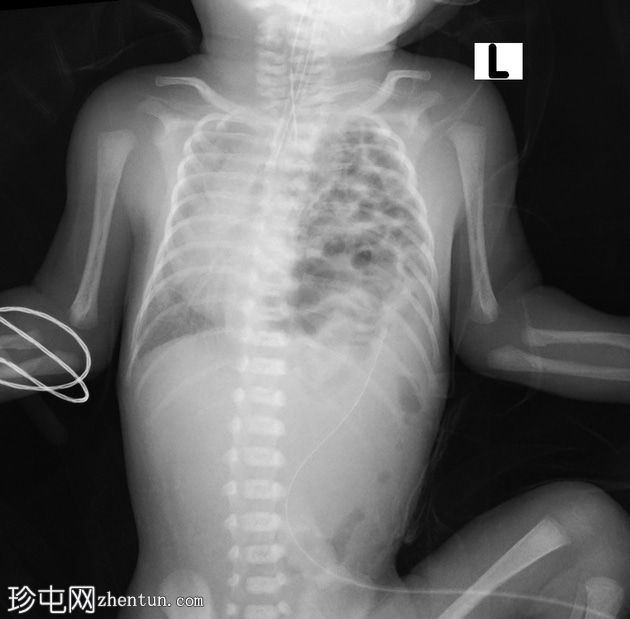

正位片

左侧胸腔可见囊性透亮区,膈下肠袢稀少。左未显影,可能发育不良。纵隔向右侧移位。脐静脉导管指向左侧,其尖端位于膈肌上方。

气管插管位置良好。

胃管尖端位于上纵隔的囊袋内。

右肺容积较小。

左侧先天性膈疝的特征,伴有食管闭锁和气管食管瘘。